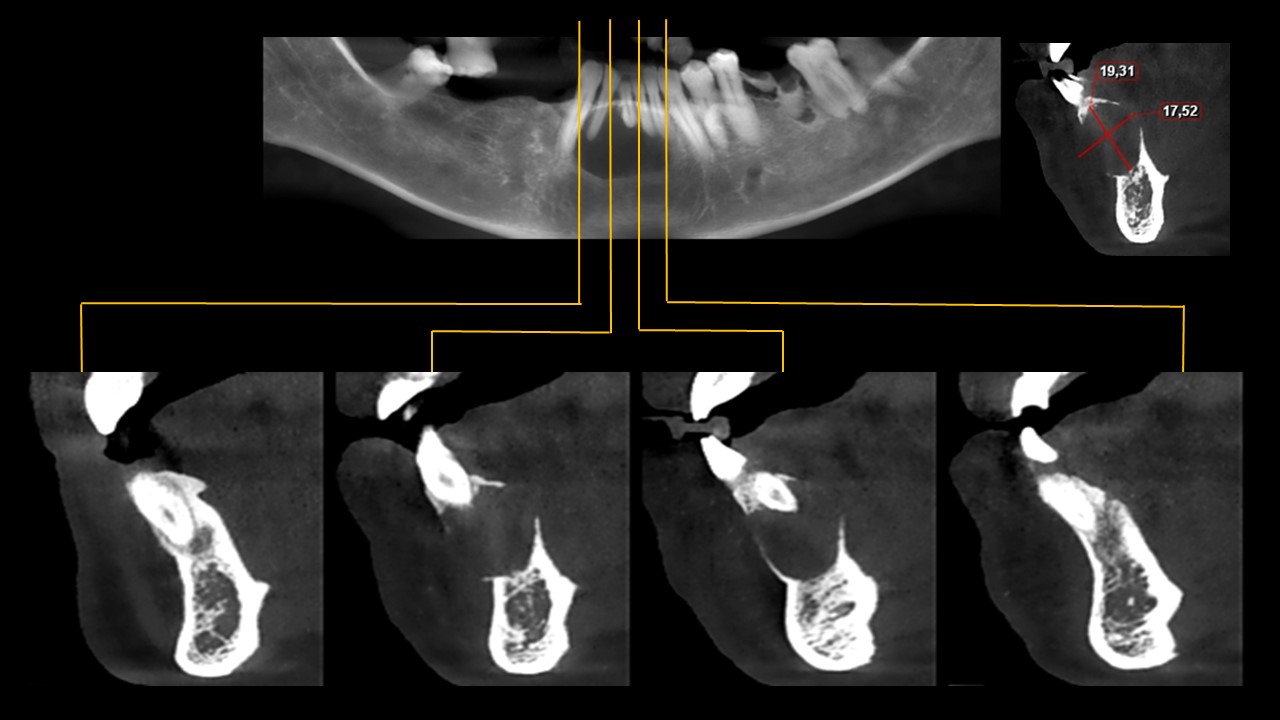

Se realiza una tomografía cone beam para evaluar mejor la región.

Figura 2

Figura 3

En los cortes axiales (Figura 2) y sagitales (Figura 3) podemos observar que la lesión es isodensa y genera el adelgazamiento y expansión de las tablas óseas lingual y vestibular.

Figura 5

En los cortes transaxiales (Figura 5) se observa el desplazamiento de las piezas mencionadas; además, la lesión tiene un tamaño de 19.31mm de alto por 17.52mm de ancho.